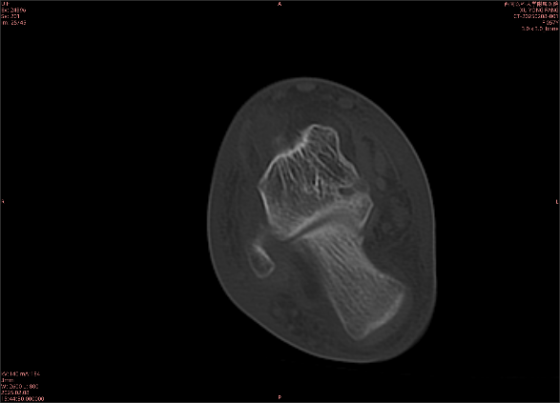

為什么DR和CT基本無法診斷?(專業(yè)科普)

由于無骨皮質(zhì)中斷,尚不足以引起X線衰減系數(shù)的明顯改變,X線平片無異常征象;CT在顯示骨皮質(zhì)及軟組織異常方面明顯優(yōu)于傳統(tǒng)X線,特別是三維重建能夠有效的評(píng)價(jià)復(fù)雜骨折,骨外傷CT檢查應(yīng)用廣泛,但CT對(duì)隱性骨折的顯示亦極為有限。

舉例圖像

圖2

專業(yè)解釋看不懂沒關(guān)系,大家看圖1和圖2就可以了,這是同一個(gè)患者跟骨的磁共振和CT圖像,圖1的紅色箭頭指示的黑線就是磁共振圖像顯示的骨折線,一目了然。而對(duì)比圖2的CT圖像上并未顯示異常。